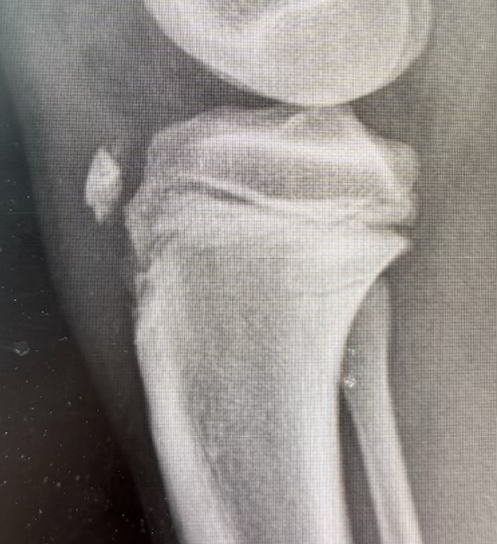

Type III

Technique

Restore articular surface

- may need to visualize joint line with arthrotomy / arthroscopy

- pass guide wires for screws into epiphysis and tibial tubercle

- image intensifer to ensure reduction / growth plate protection / no penetration to posterior neurovascular structures

- secure with AP screws in tibial epiphysis through vertical split in patella tendon

- unicortical fixation to protect popliteal artery

- restore tibial tuberosity with screws +/- washer